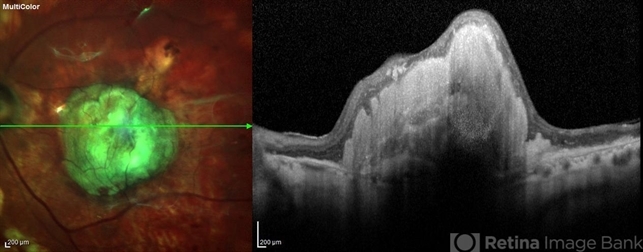

- central disciform scar

- Suber Huang, Retina Center of Ohio

- Imaging device

- Heidelberg Spectralis

- Fundus photograph and OCT scan of an 86-year-old man with long-standing type I diabetic proliferative retinopathy.